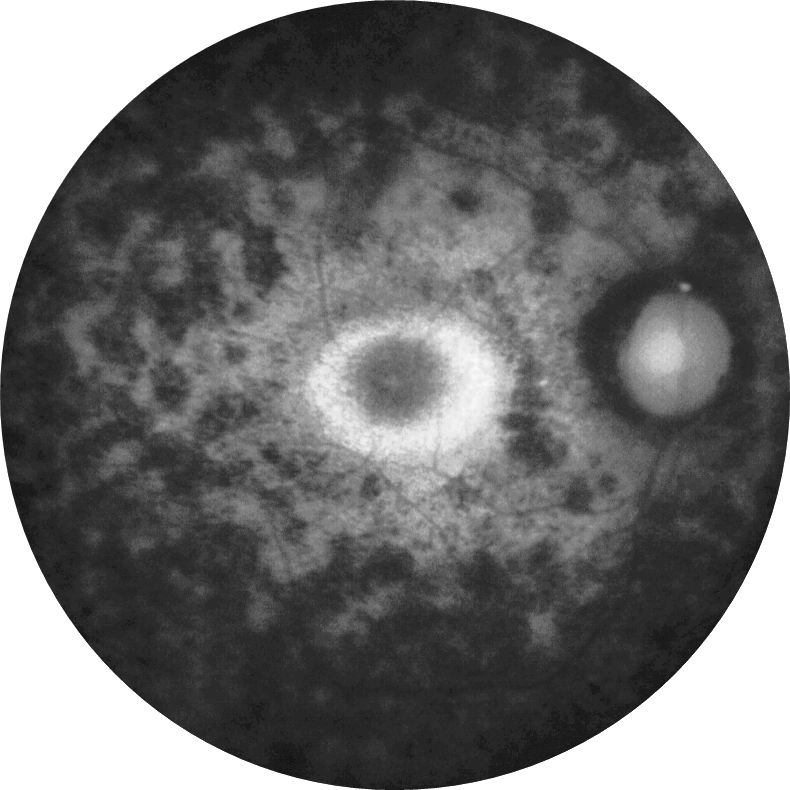

RPGRIP1 İlişkili Leber’in Konj ...

RPGRIP1 İlişkili Leber’in Konjenital Amarozisinde Kök Hücre Tabanlı Retinal Orga ...